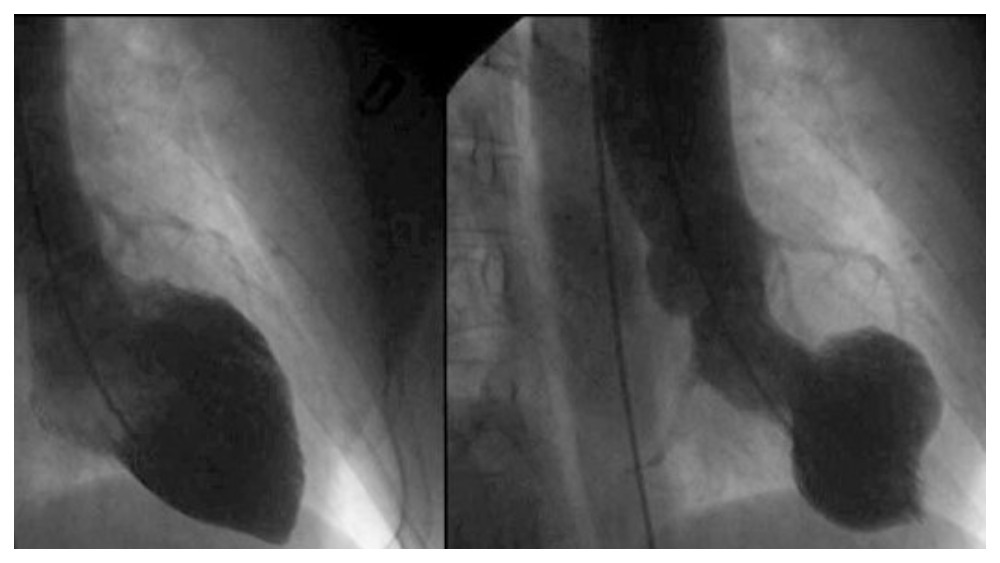

Лікарка також згадала рідкісний синдром Такоцубо, що набув розголосу як «розбите серце», коли під впливом стресу змінюється структура серця. Вона пояснила, що хоча точна причина виникнення цього синдрому досі вивчається, стресові ситуації, безсумнівно, відіграють важливу роль у його розвитку.